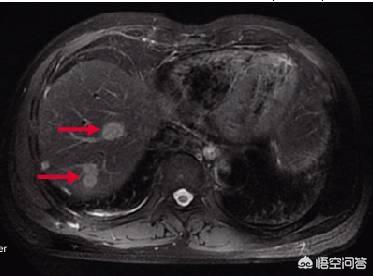

大腸癌の肝転移は非常に多く、大腸癌患者はまず腹部CTと胸部CTを撮り、肝転移と肺転移の有無を確認しなければならない。実際、血行性転移によって、腸癌は局所転移のほかに、血流にのって癌細胞が排出され、血流に乗った後、血液循環にのって肝臓に入り、肝転移が現れます。肝転移が現れたら、実は進行期であり、肝転移が全く治療できないわけではありません。肝転移が乏転移性で、転移数が比較的少なく、転移部位が比較的良好であれば、大腸と肝臓の同時切除で根絶することができますが、転移が比較的大きい場合は、全身化学療法でコントロールする必要があります。

大腸癌の肝転移の発生率は高く、約50〜70%で、手術後あるいは以前から見つかることもある。原発巣が小さく、転移巣が大きいことも珍しくない。

腫瘍径が非常に小さく、一般に1~2mmで転移がある可能性があり、肝転移がなく腫瘍が非常に小さい場合は、TNM病期分類ではI期の患者である可能性が高く、簡単な手術で5年生存率が90%以上になり、完治する可能性が非常に高いが、肝転移が起こると状況が悪くなる。